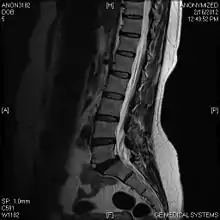

A limbus vertebra is a bone tubercle formed by bone trauma on a vertebral body, bearing a radiographic similarity to a vertebral fracture. The anterior-superior corner of a single vertebra is the common site for this defect although it can also be seen at the inferior corner as well as the posterior or anterior margin. Anatomically, it is assumed to be an intra-vertebral body herniation of the disc material occurring during adolescent growth spurt when the ring apophysis has not yet fused. It was first described by Schmorl in 1927[1] and later in detail by Leif Sward and Adad Baranto.

Viewed in a lateral radiograph, it appears as a triangular shaped bone fragment, not unlike an anterior lip fracture, but with softer edges.

Limbus vertebra is not always symptomatic, but severe cases may lead to more serious pathological conditions and chronic pain. In rare instances, a posterior limbus vertebra has been described causing radiculopathy due to nerve root compression. [2]